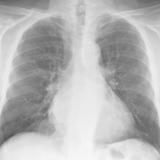

Mitral Valve Disease

Album: Mitral Valve Disease

Date: 03/17/2004

Size: 30 items

Views: 42243